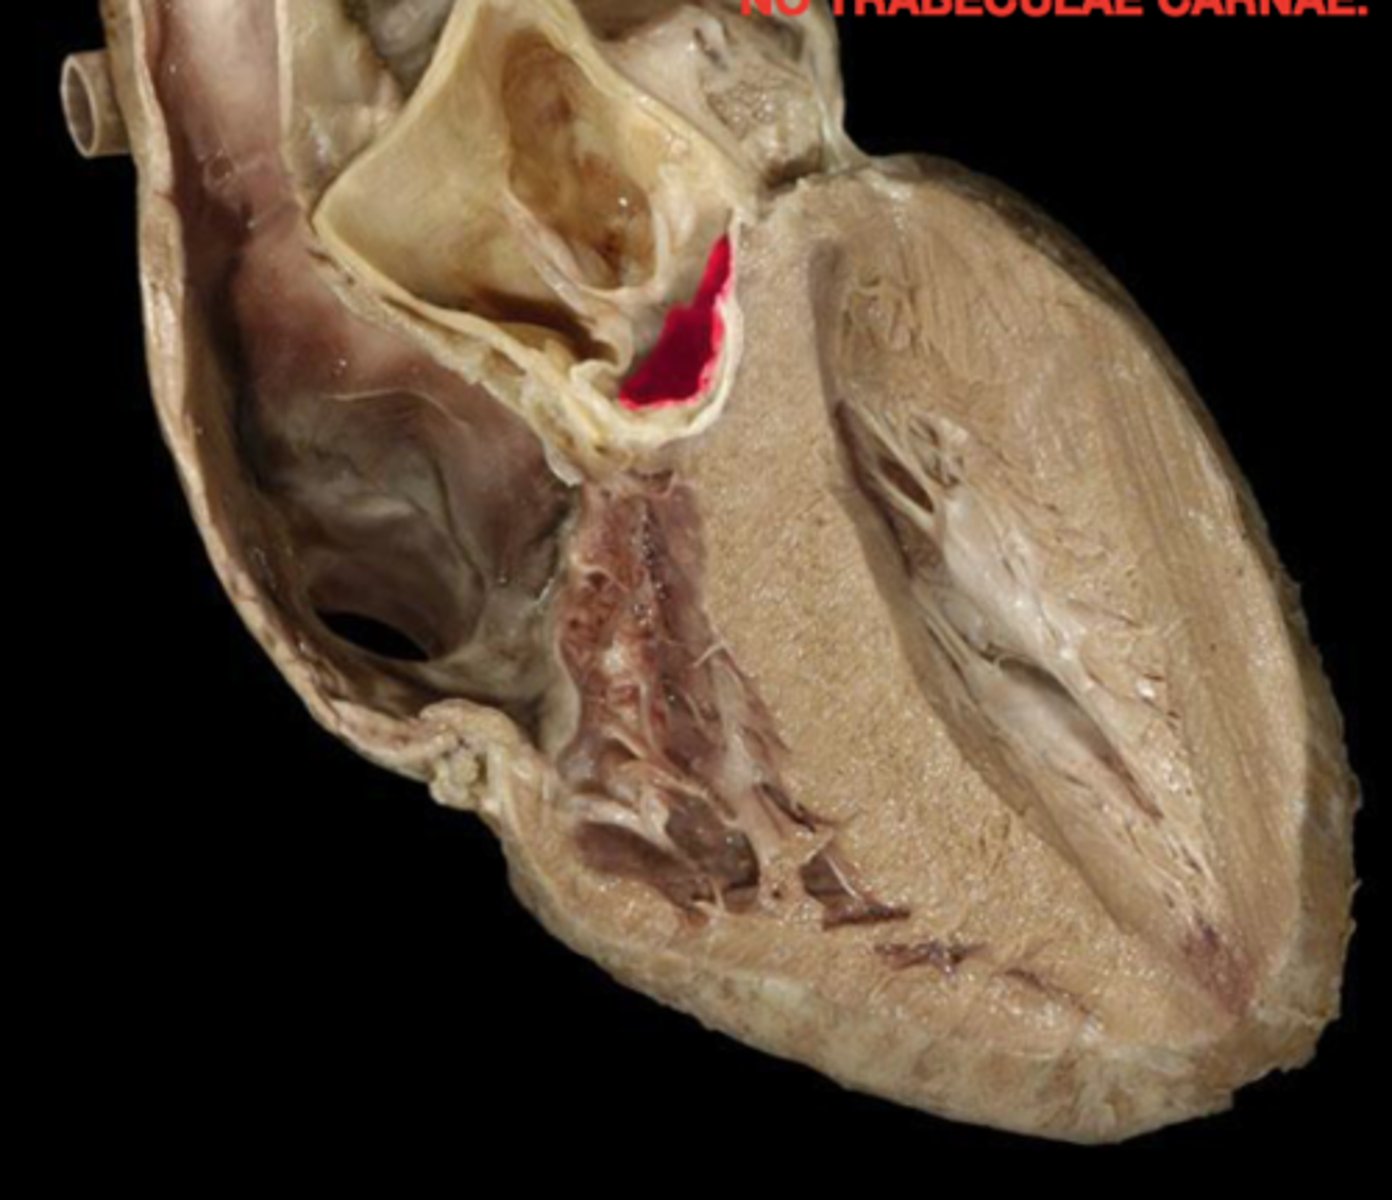

Trabeculae carneae muscle

Structure. Beef jerky, meat.

Left ventricle

Chamber, DH. TA also pinches.